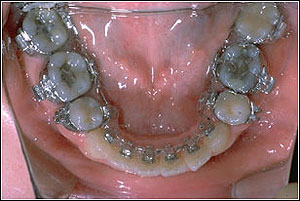

@Step by Step Treatment Procedures

STEP 1. Leveling

TMA018, 0175*0175